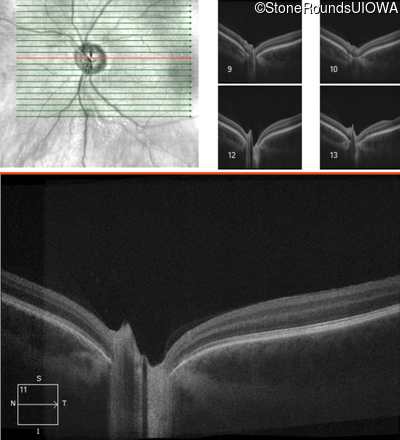

Age at visit: 17 years

OD OS

This 17 year old male had normal vision until about 6 months earlier when he began to lose central vision. The left eye may have been affected prior to the right eye.

Diagnosis & molecular findings

Leber Hereditary Optic Neuropathy MT-ND4 11778 A>G   MT